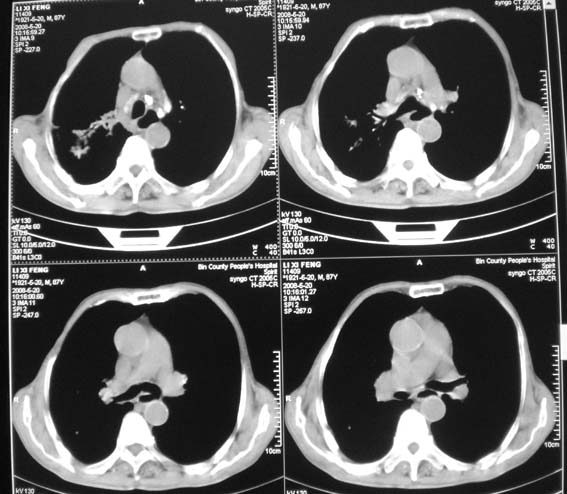

男,87岁,咳嗽、发烧、有黄痰,胸片示肺结核。

考虑继发型结核伴右上霉菌球形成。

继发性肺结核,真菌感染,不出外占位性病变,建议治疗后复查

右肺上叶尖后段片状不规则致密影,密度欠均匀,相邻胸膜肥厚,纵隔内见多发肿大、钙化淋巴结,考虑为结核,部分坏死